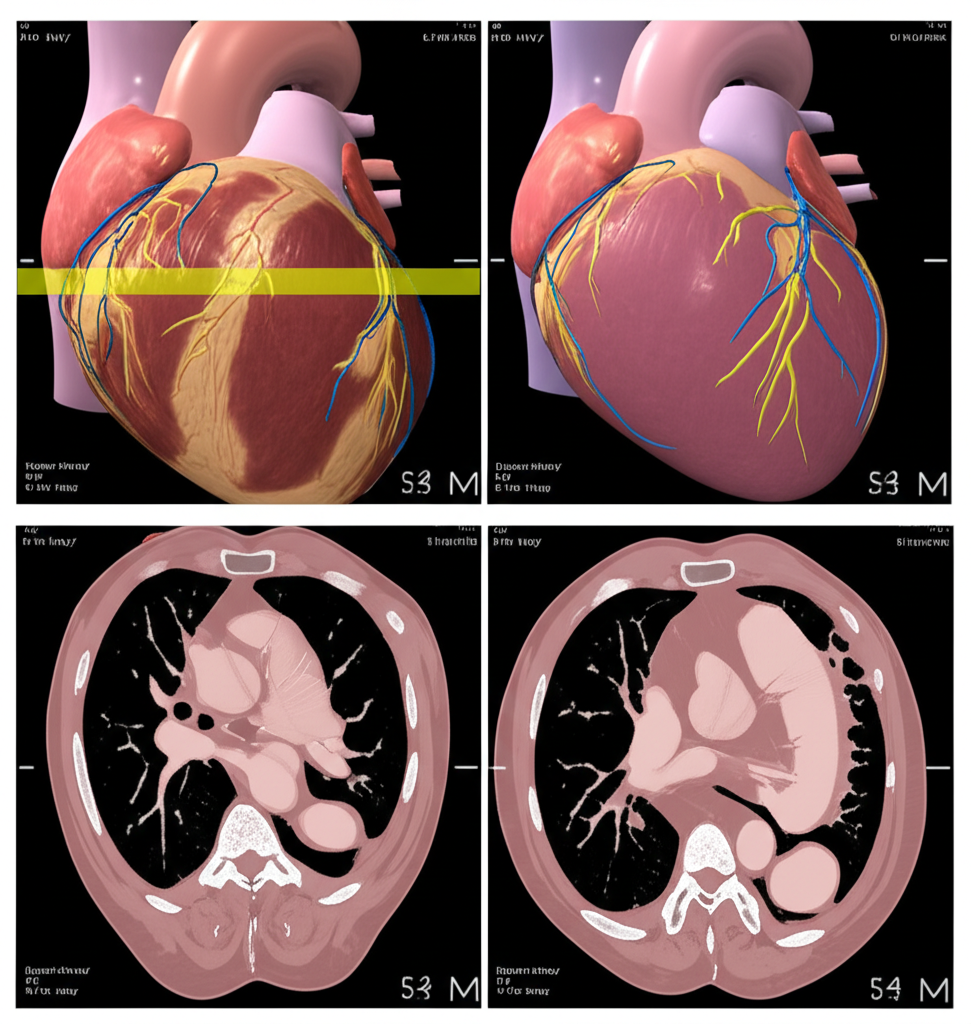

심장 CT(Computed Tomography)는 컴퓨터 단층 촬영 기술을 이용하여 심장의 단면 영상을 얻는 검사입니다. 기존의 엑스레이 촬영보다 훨씬 더 자세하고 정확한 이미지를 제공하여, 심장 질환의 조기 진단과 치료 계획 수립에 큰 도움을 줍니다. 심장 CT는 특히 관상동맥 질환, 심장 판막 질환, 심근 질환 등 다양한 심장 질환을 진단하는 데 유용합니다.

- 관상동맥 질환 진단: 관상동맥 CT는 관상동맥의 협착이나 폐쇄 여부를 정확하게 진단할 수 있습니다. 특히, 칼슘 스코어링을 통해 동맥경화의 정도를 평가하고, 향후 심혈관 질환 발생 위험을 예측할 수 있습니다.

- 심장 구조 평가: 심장의 크기, 모양, 위치 등을 정확하게 파악하여 심장 비대, 심방중격결손, 심실중격결손 등 선천성 심장 질환이나 심장 구조 이상을 진단할 수 있습니다.